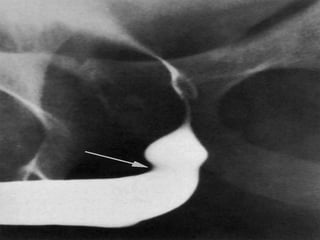

Retrograde urethrogram : resistance to passage of cm at the region of ext.sphincter

resulting in dilatation of the anterior urethra d/t pressure of injection

Retrograde urethrogram :resistance to passage of cm at the region of ext.sphincter resulting in dilatation of the anterior urethra d/t pressure of injection